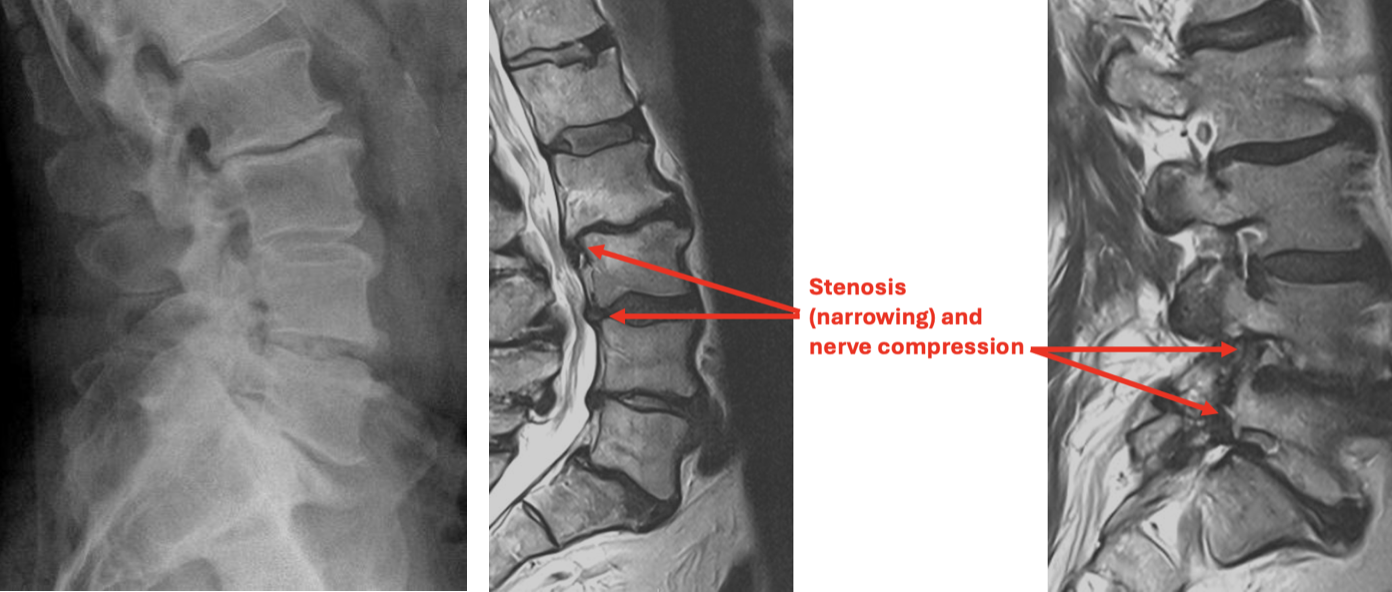

Surgical treatment to relieve back and leg pain caused by disc degeneration, spinal stenosis, instability and spinal deformity (scoliosis).

Interbody fusion is a surgical procedure that removes a painful lumbar disc and replaces it with a device to allow bone to grow across the disc space creating a fusion. The device stabilizes the collapsed and degenerated disc and restores stability to the segment, decreasing spinal pain. ALIF is done through a small incision in the lower abdomen and the spine is approached from the front. LLIF is done through a small incision in the side of the abdomen. Posterior fusion is done from the back.

Laminectomy (if needed)

- In some cases, additional work will be needed to remove all of the bone spurs that are causing the narrowing (stenosis) of the spinal canal.

- A 1-2 inch incision is made in middle of your lower back. After carefully moving the muscle tissue, a small retractor is placed to expose the back of the spine.

- The bone and ligament tissue forming the "rooftop" of the spinal canal is removed to relieve pressure on the nerves.